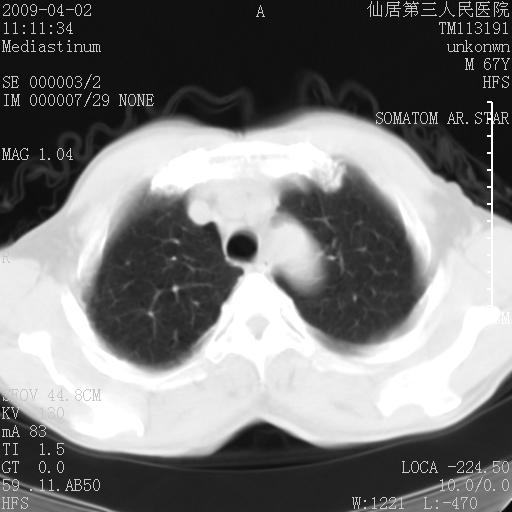

患者老年男性,乏力畏寒来诊,摄胸片示右下肺感染性病变,抗炎两周后复查胸片,无好转有进展。

后做ct平扫表现如下:

考虑右肺炎症可能性大,不除外细支气管肺泡癌

是否还要考虑肺间质纤维化,建议hrct扫描。

病灶呈蜂窝征,纵隔多个淋巴结肿大;肺泡癌需考虑

肺炎症可能性大,不除外细支气管肺泡癌

我认为普通的感染应该可以除外,间质性肺炎可能性较大,但如何解释纵膈的淋巴结肿大呢

考虑双肺间质性改变(间质纤维化?)伴右肺下叶感染。